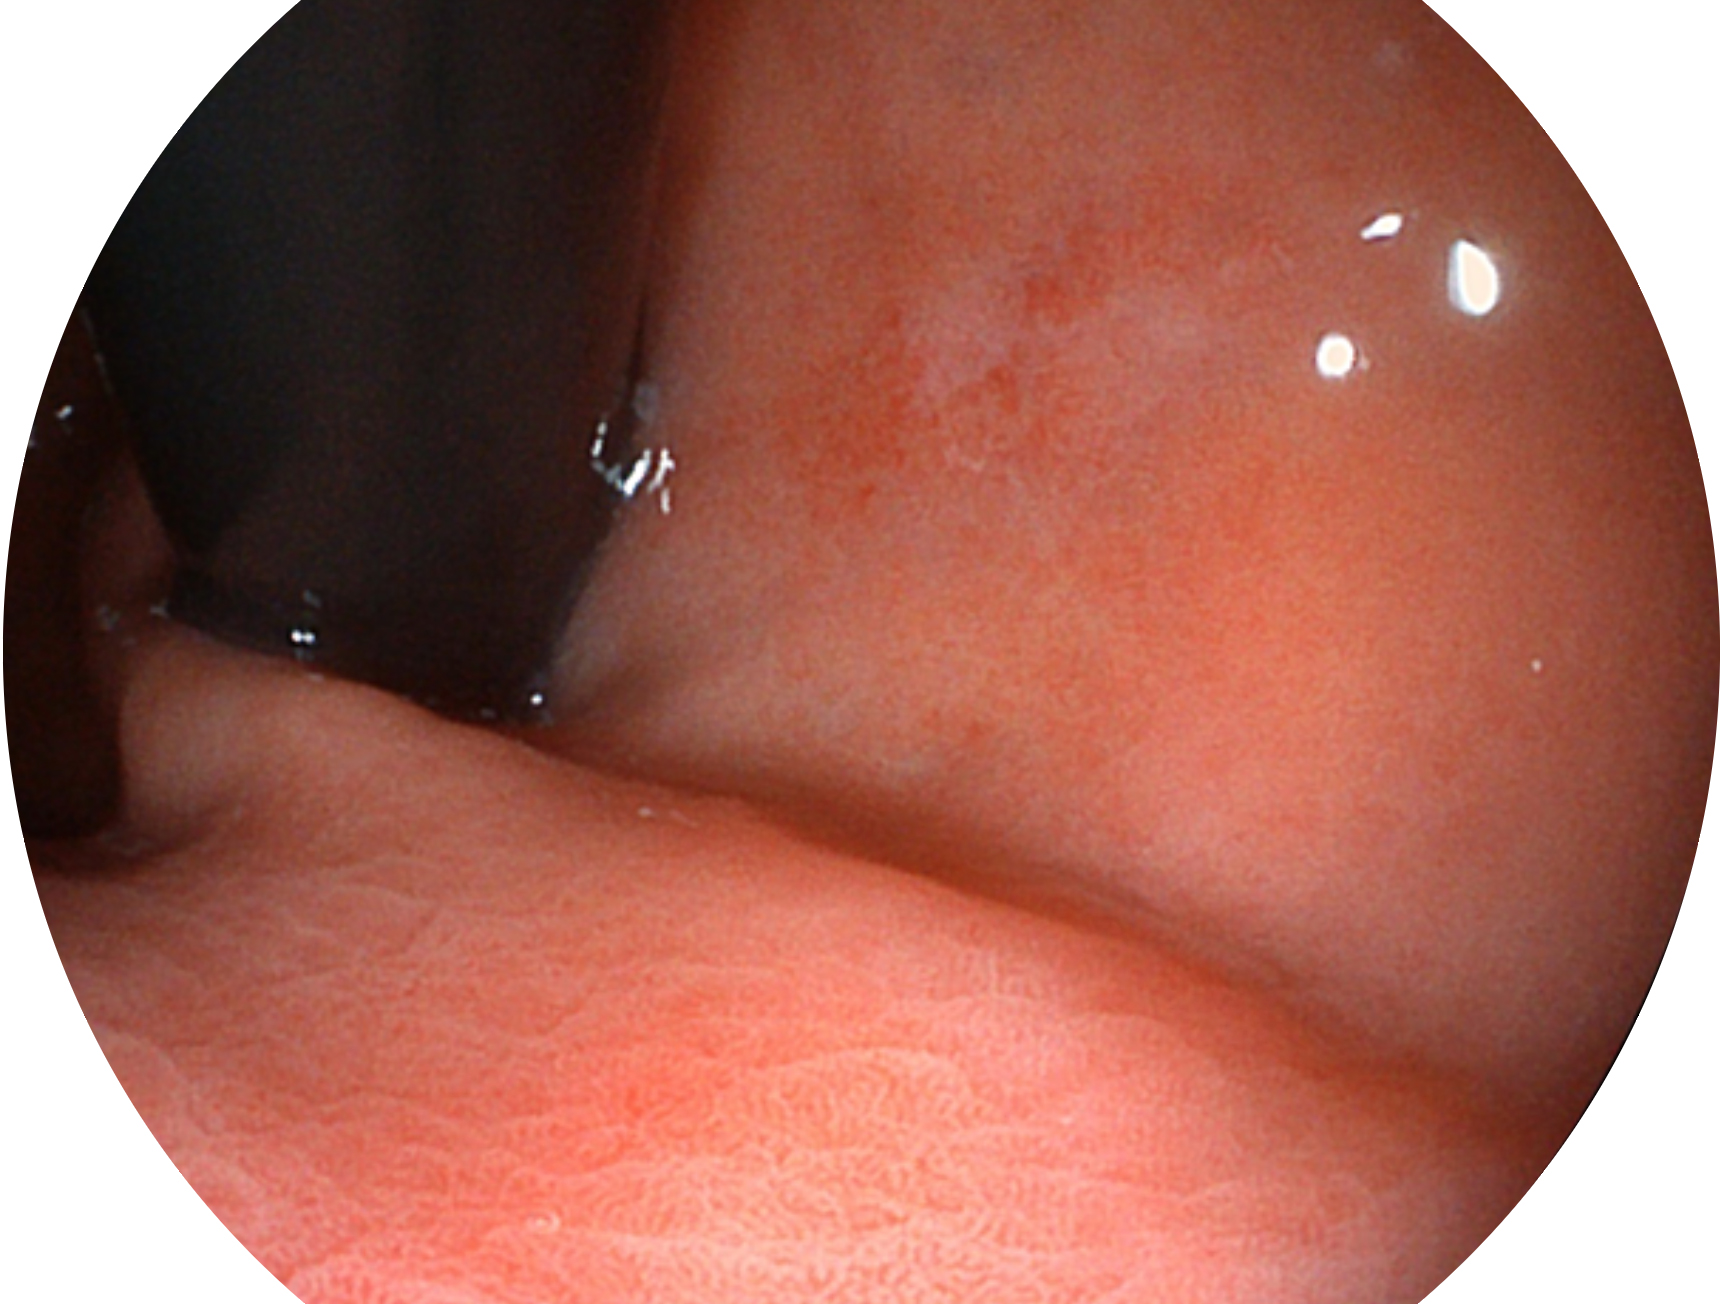

美狮贵宾会官网新开发的内镜染色技术,主要是基于多波长LED 光源的开发,VLS-55Q 四波长LED 光源是由四个不同颜色的LED光按照相应照明模式所规定的特定发光比例进行合束后形成,合束后形成的照明光的光谱由红光、绿光、蓝光及蓝紫光这四个不同的波段范围构成。具有更高光谱自由度,通过光谱比例的控制,实现了聚谱成像技术,英文全称为“Spectral Focused Imaging, SFI”,缩写为“SFI”和光电复合染色成像技术,英文全称为“Versatile Intelligent Staining Technology, VIST”,缩写为“VIST”。